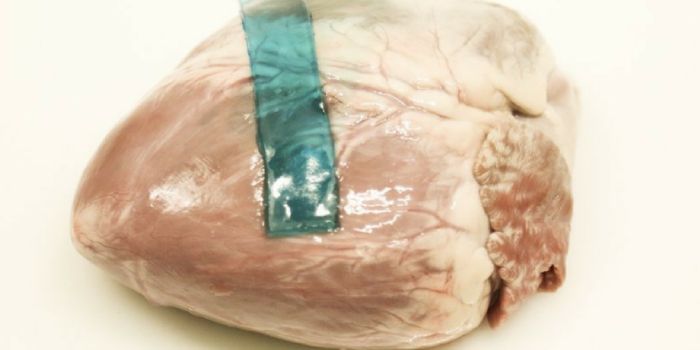

JAN 04, 2022Clinical & Molecular DXAs early as 3000 BC, ancient Egyptians described the use of sutures for drawing open wounds shut to facilitate he ...